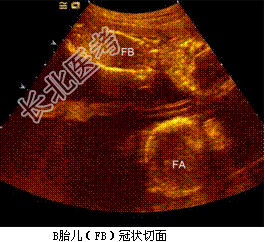

- [材料题] 孕妇,30岁,孕2产0孕22周。超声(孕12周):宫内妊娠,单绒毛膜囊双羊膜囊双活胎,A胎儿NT0.32cm,B胎儿NT0.12cm。孕22周复查超声如下图。

- 简答题1、根据上述声像图,试描述。